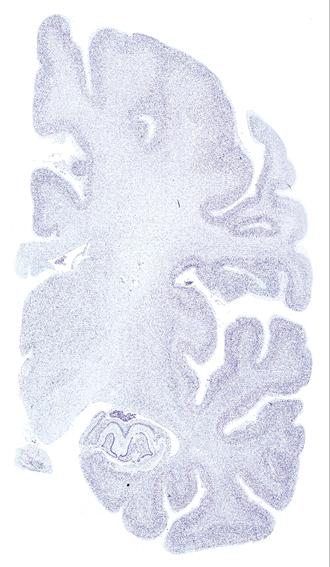

Hi-Resolution Sections · Cells (Nissl Staining) · Virtual Microscopy

Frontal sections (Nissl) from the Atlas Brain: Gallery Slice Single

16,0 mm

Slice ID: r3-0803

Plate NR: ca 34

Position: 16,0 mm